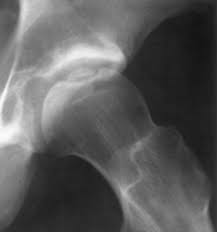

Osteochondritis dissecans of the hip

Osteochondritis of the acetabulum

Osteochondritis of the acetabulum.

Osteochondritis dissecans describes a focal lesion of the cartilage and subchondral bone. It affects the femoral head more commonly than the acetabulum. The cause is usually a combination of trauma and local vascular disruption. It can occur after known hip conditions such as Perthes disease, AVN, and hip dysplasia. It can cause pain and mechanical problems including clicking and loose bodies. X-rays and MRI show the lesion well.